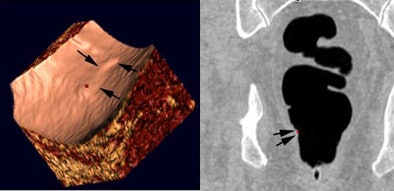

![]() |

| CAD can help: Before CAD, two readers incorrectly reported a bulbous fold as cancer, while only one reader called it a positive finding post-CAD. |

| CAD can hurt: Before CAD, a reader correctly dismissed redundant mucosa in the rectum (hemorrhoid). However, after CAD incorrectly marked the finding as positive, the reader incorrectly reported it as a small rectal polyp. |